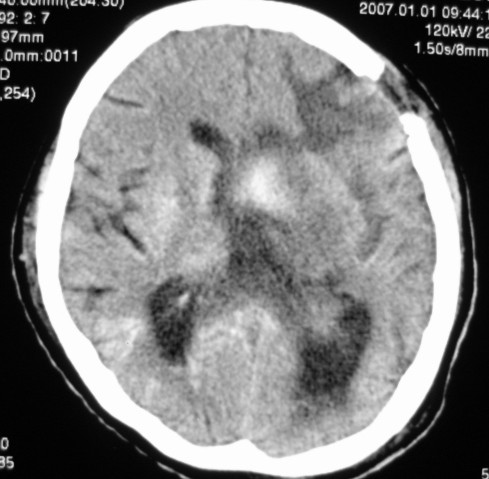

第一次ct片脑出血术后,出血吸收期。第二次ct 片左颞顶枕部及右颞顶部有脑回样高密度影。考虑珠网膜下腔出血。脑出血术后改变,脑出血恢复期 并脑积水。

第一次ct片脑出血术后,出血吸收期。第二次ct 片左颞顶枕部及右颞顶部有脑回样高密度影。考虑珠网膜下腔出血。脑出血术后改变,脑出血恢复期 并脑积水

是蛛网膜下腔出血么?蛛网膜下腔出血应该在脑沟里,而此高密度影是沿脑回分布,应该是脑膜感染后钙化灶形成。

应该是脑膜感染后钙化灶形成。脑出血术后改变;脑积水

应该是脑膜感染后钙化灶形成。脑出血术后改变;脑积水. 支持

考虑脑膜感染后的改变,术后改变。

应该是脑回钙化,不是出血

脑回状高密度影,首先要考虑脑颜面血管瘤病,不知高密度区ct值多少,对于鉴别是蛛网膜下腔出血还是钙化有意义,只是病人半月前“钙化”还较局限,因此还是考虑与脑出血有关。当然要密切结合病史及临床,增强扫描有意义。

考虑是脑回钙化,不是出血,什末样的蛛网膜下腔出血是这样的?我没见过!考虑脑炎性钙化,要结合病史!

两次的片都有,第二次比第一次的明显